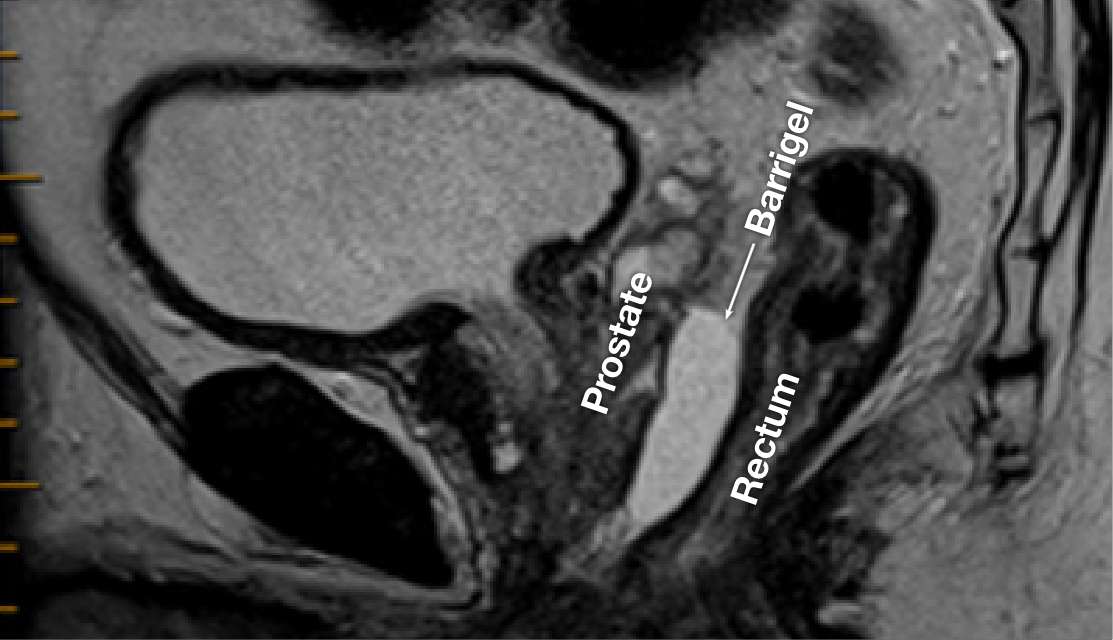

MRI IMAGES

MR image courtesy of Prof Michael Chao, MBBS (Hons), FRANZCR, AFRACMA, DMedSc, Radiation Oncologist; Victoria, Australia